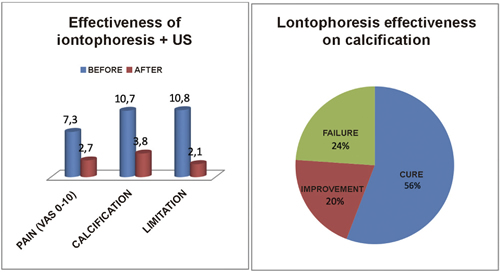

The mean initial pain was 7.3 points on the VAS scale, and it decreased significantly (p = 0.0000) after treatment to 2.7 points (Figure 3). The initial mean size of the calcifications was 10.7 mm and it decreased significantly (p = 0.0000) to 3.8 mm after treatment (Figure 3).

Fig. 3. Effectiveness of iontophoresis on pain (VAS 0-10), calcification size (mm) and functional limitation (%) in patients with calcific tendinitis of the shoulder.

The change in calcification is considered an outcome variable, which considered the disappearance (decrease of more than 75%), decrease (reduction between 25-75%) or no decrease (reduction of less than 25%) of the calcification. This allows us to evaluate treatment as success/cure, improvement, or failure, respectively. This represented a success/cure rate of 55.7% (n = 77), improvement of 20.2% (n = 28), and failure of 23.9% (n = 33) (Figure 3).

After treatment, only 3 patients (2.1%) out of the 15 patients with functional limitation (10.8%) remained with limitation, for which they required manual therapy (20 sessions on average) for their complete recovery (Figure 3).